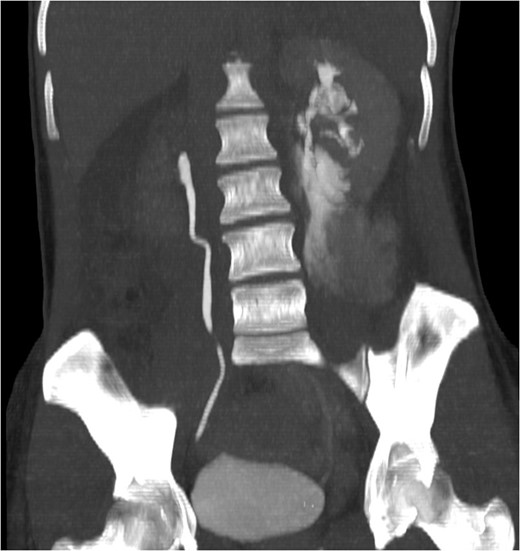

Coronal view reconstructions using maximum intensity projection, showing proximal ureteric leak of contrast.